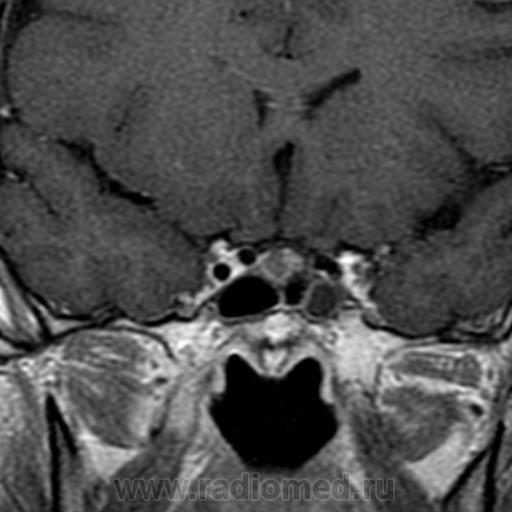

Представлены томограммы пациентки Б., 23 лет. Исследование назначено врачом-эндокринологом после лабораторного обледования. Высокие цифры пролактина. Пациентка существенных соматических жалоб не предъявляет. Акромегалии нет. Жалобы на невозможность забеременеть, нарушения менструального цикла. После проведения исследования в стандартных режимах и в режиме динамического сканирования с в/в контрастным усилением 20 мл ОМНИСКАН в правой доле гипофиза визуализируется дополнительное образование неправильной формы отстающее в накоплении контрастного вещества от здоровой ткани гипофиза. Выставлен диагноз: Микроаденома (пролактинома) гипофиза. Привожу данный клинический случай помятуя о разговоре в форуме.

Обратите внимание, коллеги, аденома не деформирует дно турецкого седла. Мне даже кажется, что за счет легкой асимметрии правая половина гипофиза расположена чуть выше левой.